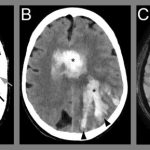

One of the most exciting facets of Aurora’s evolving healthcare scene is the application of AI in diagnostic imaging. Collaborative projects, such as the partnership between Advocate Health and Aidoc, have deployed the aiOS™ platform to significantly improve diagnostic accuracy across specialties like radiology, cardiology, neurovascular, and vascular care. By integrating a collection of FDA-cleared AI algorithms, clinicians can now pick up subtle abnormalities and diagnose conditions with a reported 94% accuracy rate compared to older techniques.

Advancements in technology have provided Aurora’s healthcare institutions with tools that upgrade patient care to a new level. AI-enhanced imaging devices allow for quicker detection of conditions like rib fractures and cervical spine injuries. Additionally, AI solutions support optimized radiation dosing in imaging procedures, thereby significantly reducing patient exposure while maintaining diagnostic precision.

Aurora’s healthcare providers are getting into the nitty-gritty of using AI to effectively transform patient care. Medical institutions have implemented AI to address issues ranging from image analysis to automated reporting. For instance, initiatives by institutions such as Northwestern Medicine have incorporated AI to expedite the reading of X-ray images and rapidly identify anomalies that suggest conditions like COVID-19 or other urgent health issues.

In many cases, the goal is to reduce those overwhelming challenges associated with long wait times and the potential for diagnostic errors. AI deployments in radiology have been particularly beneficial; the technology helps identify anomalies that might otherwise be missed even by experienced professionals. Additionally, the use of AI to optimize radiation dosing not only makes the diagnostic process more efficient but also lessens the risk posed to patients by reducing unnecessary exposure to high levels of radiation.